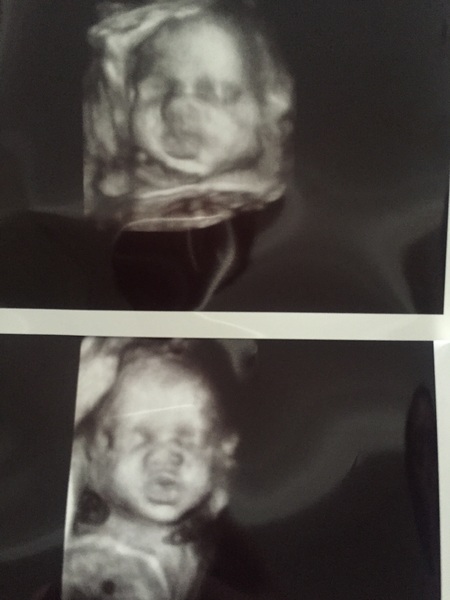

I have my vaccine booked for Tuesday coming.. 3D scan today- excited!

Can't wait to meet him!! Inlove!

Lovely scan pics!

Lovely pics Danni how was it seeing baby in 3d on the screen?

It was amazing bobby! I'm so glad I did it now. He even gave us a Lil smile